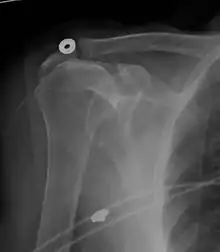

Diagnostic modalities, dependent on circumstances, include X-ray, MRI, MR arthrography, double-contrast arthrography, and ultrasound. Although MR arthrography is currently considered the gold standard, ultrasound may be most cost-effective.[31] Usually, a tear will be undetected by X-ray, although bone spurs, which can impinge upon the rotator cuff tendons, may be visible.[32] Such spurs suggest chronic severe rotator cuff disease. Double-contrast arthrography involves injecting contrast dye into the shoulder joint to detect leakage out of the injured rotator cuff[33] and its value is influenced by the experience of the operator. The most common diagnostic tool is magnetic resonance imaging (MRI), which can sometimes indicate the size of the tear, as well as its location within the tendon. Furthermore, MRI enables the detection or exclusion of complete rotator cuff tears with reasonable accuracy and is also suitable to diagnose other pathologies of the shoulder joint.[34]

MRI

Magnetic resonance imaging (MRI) and ultrasound[42] are comparable in efficacy and helpful in diagnosis although both have a false positive rate of 15–20%.[43] MRI can reliably detect most full-thickness tears although very small pinpoint tears may be missed. In such situations, an MRI combined with an injection of contrast material, an MR-arthrogram, may help to confirm the diagnosis. It should be realized that a normal MRI cannot fully rule out a small tear (a false negative) while partial-thickness tears are not as reliably detected.[44] While MRI is sensitive in identifying tendon degeneration (tendinopathy), it may not reliably distinguish between a degenerative tendon and a partially torn tendon. Again, magnetic resonance arthrography can improve the differentiation.[44] An overall sensitivity of 91% (9% false negative rate) has been reported indicating that magnetic resonance arthrography is reliable in the detection of partial-thickness rotator cuff tears.[44] However, its routine use is not advised, since it involves entering the joint with a needle with potential risk of infection. Consequently, the test is reserved for cases in which the diagnosis remains unclear.